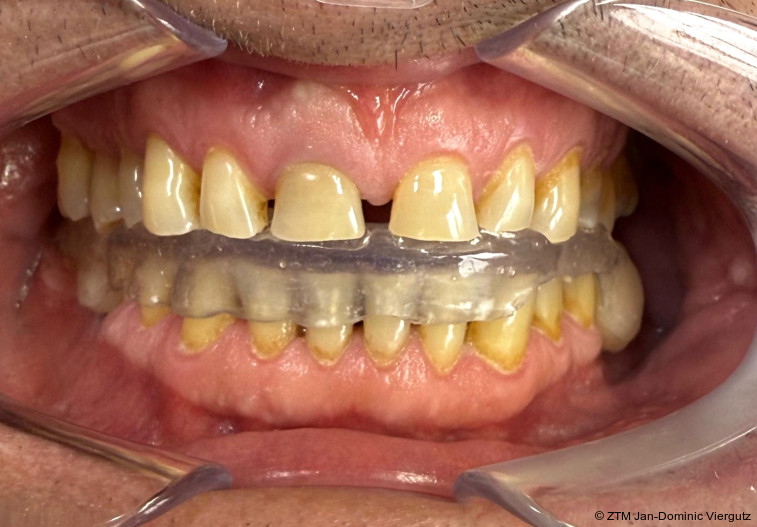

Nach der erfolgreichen Eingliederung der Michigan-Schiene (Erkodur, Erkodent) und dem deutlichen Rückgang der Kiefergelenkschmerzen wurde die Behandlung gemäß dem Therapieplan fortgesetzt. Zunächst erfolgte die erneute Wurzelbehandlung am Zahn 11, gefolgt von der schablonengeführten Implantation (DTX Studio Clinic, Nobel Biocare) von drei Implantaten (NobelReplace, Nobel Biocare) im Unterkiefer (36, 37 und 46). Alle chirurgischen Maßnahmen wurden in Dämmerschlaf-Narkose unter Begleitung eines Anästhesisten durchgeführt.

Nach einer Einheilzeit von fünf Monaten zeigten sich stabile Verhältnisse: Die Kiefergelenkschmerzen waren weiterhin nicht vorhanden, die Implantate wiesen eine sichere Osseointegration auf und Zahn 11 blieb beschwerdefrei. Daraufhin konnte die Präparation der Zähne unter erneuter Narkose erfolgen. Die digitale Abformung wurde mit dem iTero-Intraoralscanner (Align Technology) vorgenommen und ermöglichte eine präzise Erfassung der klinischen Situation. Direkt im Anschluss wurde das Provisorium mittels tiefgezogenen Formteils (Erkodur, Erkodent) erstellt und eingesetzt.